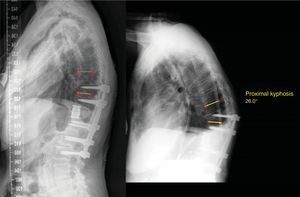

Late mechanical surgical complications (19.3%): proximal (Fig. 7) or distal adjacent level syndrome, pseudoarthrosis, instrumentation failure (pull-out) or implant breakage.